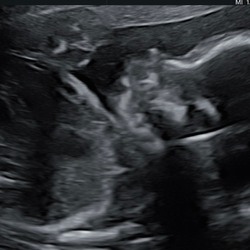

Bij 32 weken bleek de groei toch wel wat achter te lopen en ze kon op dat moment niet een goed beeld krijgen door de ligging van ons meisje, maar hier werd het buikje op p3 geschat.

Dus toch doorgestuurd naar de gyneacoloog, hier had ik 3 dagen later een afspraak en kwam p2,3 uit de echo.

Gister de tweede echo gehad bij de gyneacoloog en nu kwam het buikje op een p1 waarde.

Ik ben nu 35+2 en haar gewicht word geschat op 1834gram op dit moment, en de gyneacoloog zei dat ze max rond de 2000gram zal zitten bij haar geboorte.